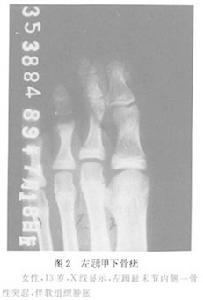

圖2 單發性骨軟骨瘤鑑別診斷:

骨軟骨瘤在手、足小骨上其X線表現類似於在長管狀骨的表現, 值得注意的是在指、指末節可有小的骨軟骨瘤存在,稱為甲下骨疣(圖2)。